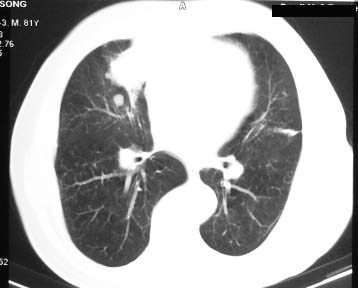

右肺中叶软组织块,其周围可见多个类圆形结节,右肺上叶尖段见斑片、索条状致影,左肺小结节,见分叶、毛刺及胸膜凹陷征。1.左肺周围型肺癌伴右肺内转移; 2.右肺上叶陈旧性结核。

老年人,适用多元论,考虑 :1、左肺周围型肺癌伴右肺内转移; 2、右肺上叶陈旧性结核。